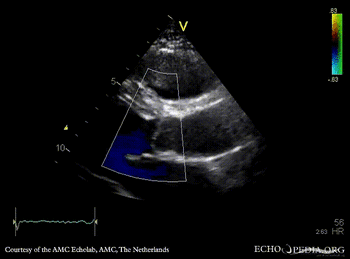

Davids procedure

Courtesy of: AMC Echolab, AMC, The Netherlands

PLAX: native aortic valve and prosthesis in ascending aorta PLAX with Color Doppler